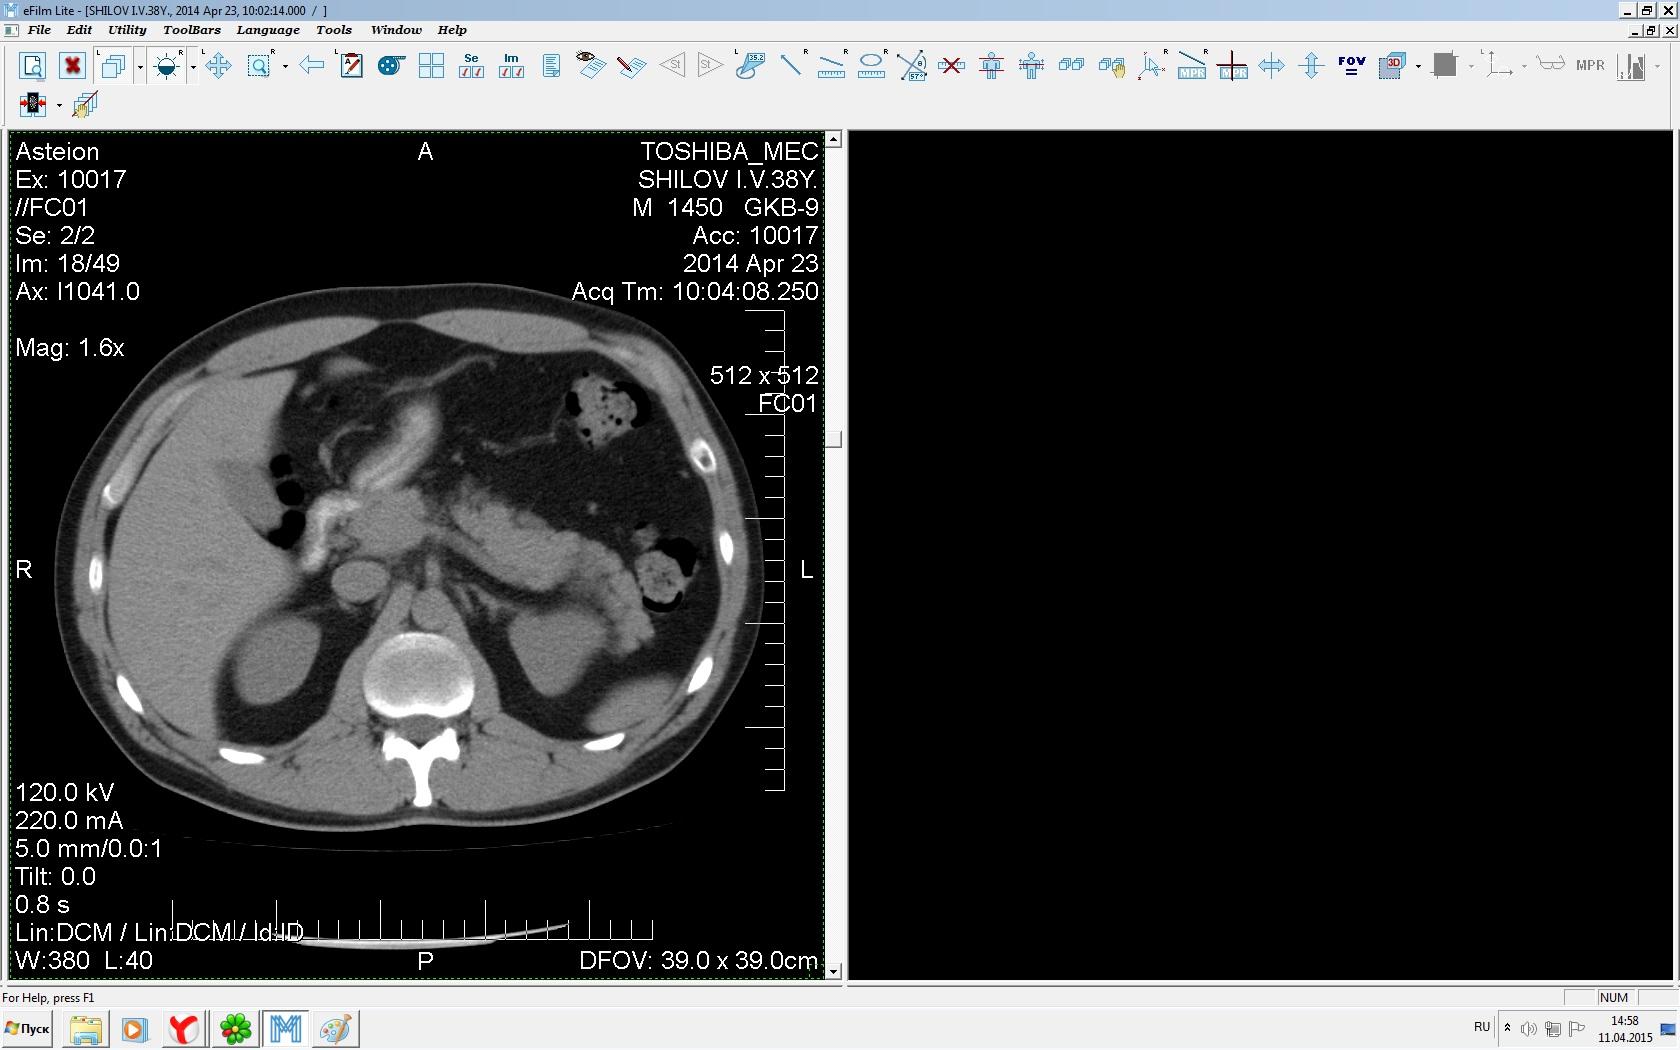

Здравствуйте. У меня киста левой почки. Из заключения: левая почка увеличена, деформирована за счёт наличия в среднем сегменте округлого жидкостного +6, +15 HU образования 66х53 мм, деформирует, поддавливает чаше-лоханочную систему. Сосудистые ножки структурные. В урологии мне сперва предложили лапароскопию, когда я лёг на операцию - изменили на полостную в связи со сложностью. Потом сказали что шансов вырезать кисту без почки практически нет. Даже если кисту удалить чудесным способом, то почка всё равно сложится и не будет работать. В итоге операцию отменили. Скажите, пожалуйста, есть ли современный метод удалить кисту и сохранить почку в моём случае? Томография почки в приложениях. Заранее благодарю.

Эту кисту можно просто пропунктировать, аспирировать и склерозировать - под местной анестезией. Ничего сверхестетственного не определяется по данным КТ. Можете написать мне на почту. aristova-tatyana@mail.ru